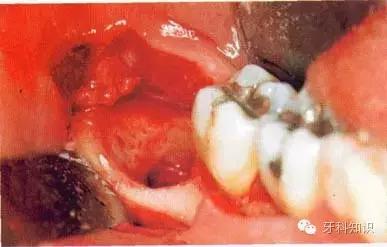

c使用纺锤形的车针( Komet - H162A.314),显露其最大周径至釉牙骨质界。车针末端应进入牙槽窝内壁

d 分牙前应认真确定分牙沟的位置:沿牙体长轴垂直(牙合)面至根分叉。用上述的车针分牙。切割至牙冠舌侧时应格外小心

e分牙已基本完成,远中牙片挺松后即可顺利取出

f 远中牙片取出后即可拔除近中部分。术后应注意牙槽嵴顶的高度。保留颊侧骨板很重要,它有利于牙槽窝和第二磨牙牙槽骨的完全重建